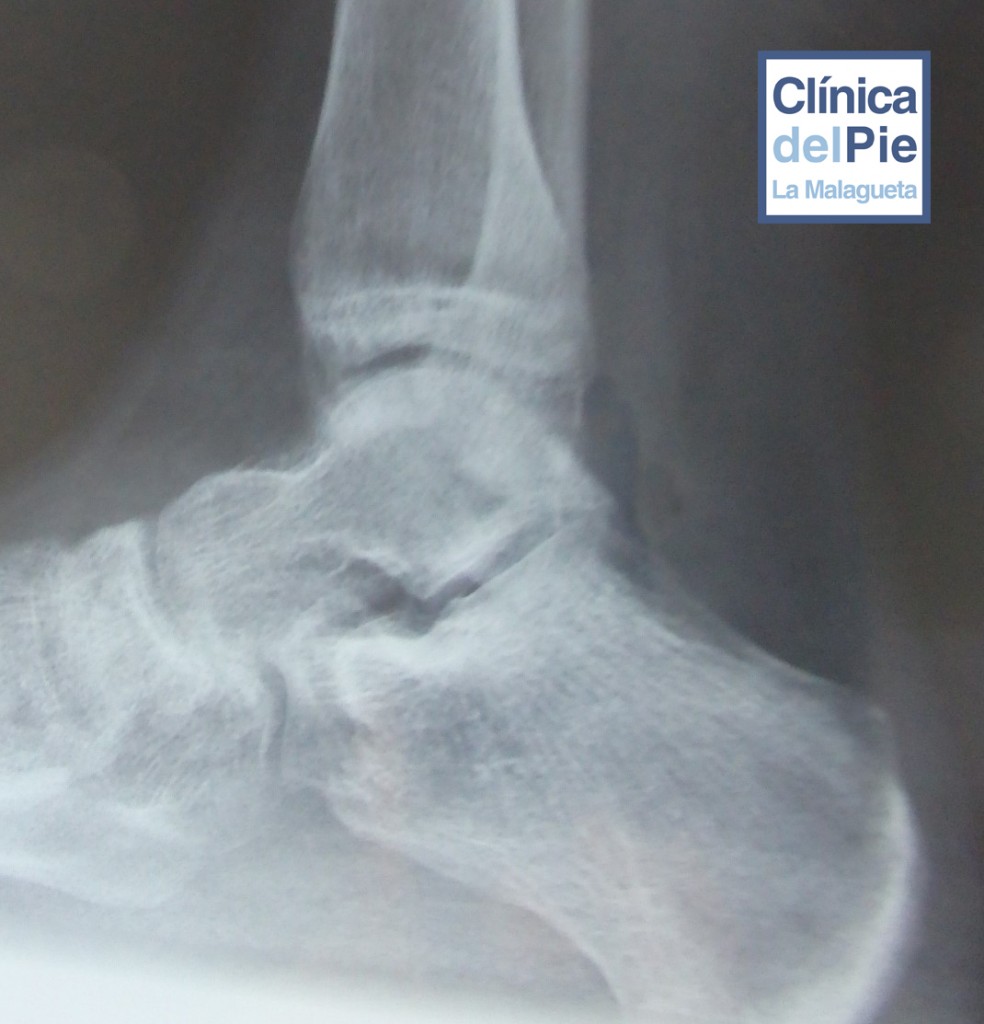

El diagnóstico inicial se hace complementando la visita a la clínica con la gammagrafía, donde se aprecia una captación del radionúclidos. La radiografía nos ayuda a orientarnos sobre en que fase se encuentra la deformidad, en función de dónde se encuentren las alteraciones óseas, aunque no ayudan a predecir el pronóstico.